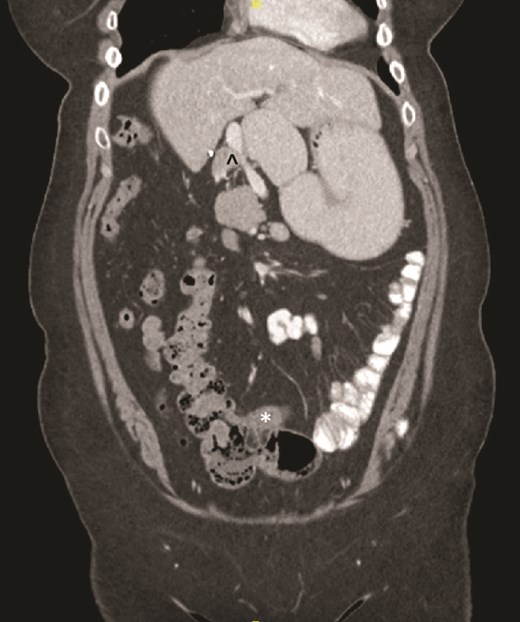

On examination, the abdomen was soft but mildly distended. Bowel sounds were heard, and the epigastrium was mildly tender. Standard bloodwork was normal. Review of an abdominal computerized tomography (CT) scan from 4 years prior showed congenital malrotation of the bowel, with the small bowel to the left of the midline and colon entirely to the right (Fig. 1). There was partial agenesis of the dorsal pancreas (Fig. 2), azygous continuation of the inferior vena cava (IVC), a retroaortic and retrocrural left renal vein, and an unremarkable spleen alongside some splenules. The PV traversed anterior to the first part of the duodenum (Fig. 3). There was relative narrowing of the distal stomach and the duodenum was nondilated.

Terminal ileum (*) seen entering cecum with completely right-sided colon and left-sided small bowel visible. PDPV also seen (^) causing partial duodenal obstruction.

Preduodenal PV seen crossing the duodenum (D) causing partial obstruction.